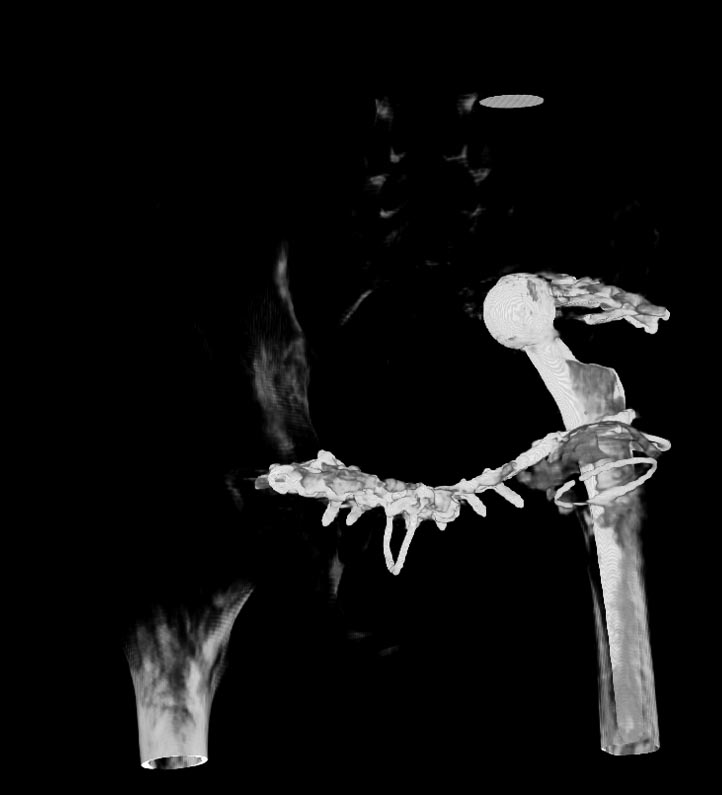

Мужчина 21 год, 2 года назад обнаружен эхиннокок костей таза, часть костей удалена сделано эндопротезирование и остеосинтез.Послеоперациооный период протекал гладко, через 6 месяцев упал, лечился консервативно, далее цепная реакция из проблем: гнойный остеомилит, свищи и лизис костей таза, на бак посеве эхинокок не обнаружен. Бедро не опорно, но больной предвигается на костылях. Картина маслом на рентгене и кт.об артродезировании думали, но диастаз большой, да и на фоне лизиса и остеопороза?????

Имя     : ct.jpg

Тип     : image/jpg

Размер  : 41371 байтов

Описание: отсутствует

Url     : http://weborto.net:8080/pipermail/ortho/attachments/20121127/db0e4c1e/attachment-0003.jpg